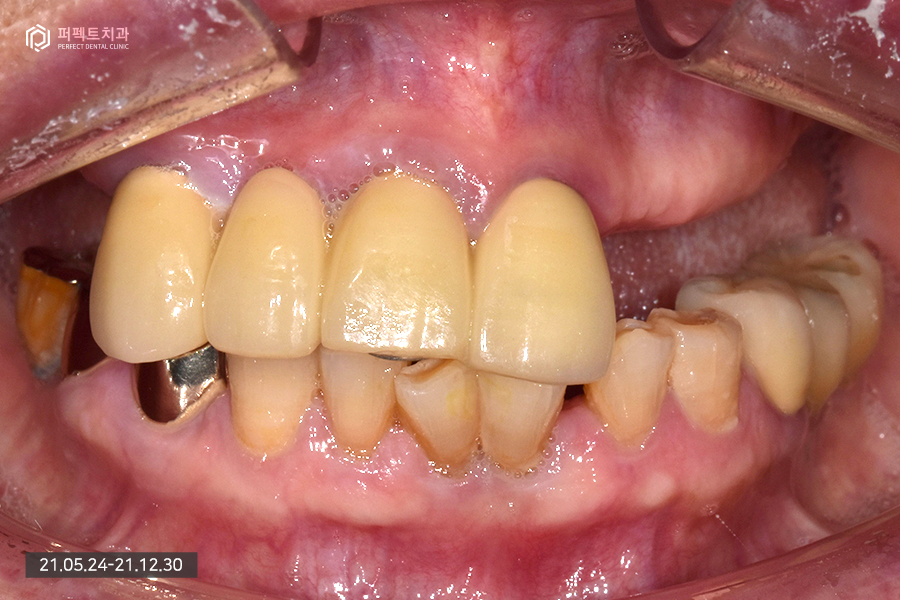

안녕하세요. 오늘은 임플란트에 관해서 살펴보겠습니다. 윗니는 전체 임플란트를 식립하는 전악 임플란트 케이스이고, 아랫니는 임플란트와 보철치료를 함께 한 케이스입니다.

내원 당시 초진 사진입니다.

80대 여성 환자분으로 연세가 많은 편이셔서 앞니는 몇 개 남지 않았고 어금니는 아예 없는 상태였습니다.

남아있는 앞니의 경우 3개가 남아있고 하나는 걸어서 사용하고 있는 상황이었는데 앞니가 심하게 흔들리고 있는 상황이라 모두 발치 하기로 결정을 하였습니다. 이런 경우 윗니는 치아가 하나도 없는 상태가 되어 전체 임플란트로 수복하게 됩니다.

아래 치아의 경우 멀쩡한 것처럼 보이지만 실제로는 그렇지 않습니다. 발치를 해야하는 치아들도 있고 치아가 없는 부분은 임플란트로 수복하기로 하였습니다.

윗니의 경우 치아가 전혀 없기 때문에 9개의 임플란트를 식립하였는데 이처럼 많은 양의 임플란트를 식립하는 경우 상황에 맞게 진료를 하게 됩니다.

위 환자분의 경우 뼈가 굉장히 약한 뼈이기도 하고 골다공증도 있으셔서 심을 수 있는 곳에 가능한 많은 임플란트를 식립하기로 하였습니다. 완성된 사진을 보면 더 명확히 아실 수 있는데요.

전악임플란트를 하신 부분을 확인해보시면 세덩어리로 완성을 했습니다. 오른쪽 파랗게 보이는 부분은 홀을 임시로 메워둔 상태입니다. 완성된 사진을 보시면 잘 치료된 것을 보실 수 있을 것입니다.